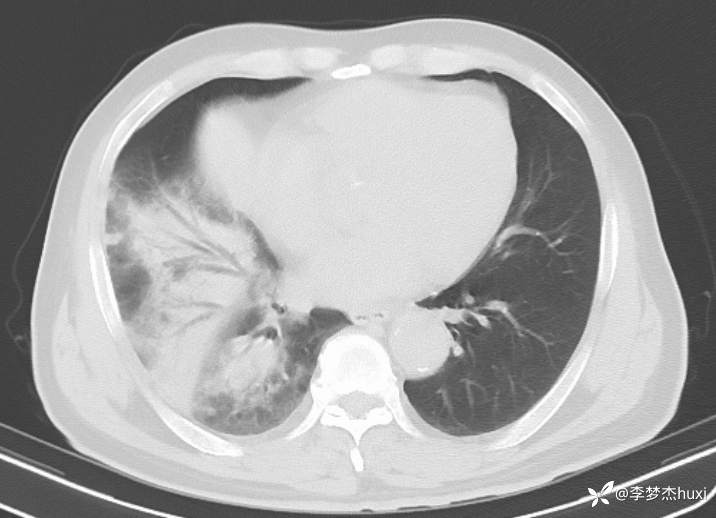

【现病史及既往史】: 1.现病史:患者老年 男,患者缘于入院前4天无明显诱因出现发热,体温最高达38.6℃,无寒战,伴咳嗽,咳痰,为黄痰,胸闷、憋气,周身酸痛,头痛,无咽痛,进食差,无胸痛及咯血,无鼻塞、流涕,无恶心、呕吐,无腹痛、腹泻,无尿频、尿急、尿痛,无血尿及腰背部疼痛,院外口服药物治疗(具体不详),症状无好转,现为求进一步诊治来诊,查头胸部CT:脑干密度欠均匀,双侧基底节区腔隙灶,脑白质稀疏,脑萎缩,鼻窦炎,右肺炎症,主动脉及冠状动脉钙化,双侧胸膜局限性增厚,甲状腺左叶密度欠均匀,建议结合临床复查。查血常规:白细胞数目11.85x109/L,C-反应蛋白241.01mg/L,中性粒细胞数目9.98x109/L,肝功能:谷丙转氨酶108U/L,谷草转氨酶110U/L,心肌酶、血糖、肾功能、钾钠氯、血脂大致正常,尿常规:蛋白质3+,酮体2+,潜血2+。心电图示:窦性心动过速。门诊以“肺炎”收住院。。

4.辅助检查:头胸部CT:脑干密度欠均匀,双侧基底节区腔隙灶,脑白质稀疏,脑萎缩,鼻窦炎,右肺炎症,主动脉及冠状动脉钙化,双侧胸膜局限性增厚,甲状腺左叶密度欠均匀,建议结合临床复查。查血常规:白细胞数目11.85x109/L,C-反应蛋白241.01mg/L,中性粒细胞数目9.98x109/L,肝功能:谷丙转氨酶108U/L,谷草转氨酶110U/L,心肌酶、血糖、肾功能、钾钠氯、血脂大致正常,尿常规:蛋白质3+,酮体2+,潜血2+。心电图示:窦性心动过速。